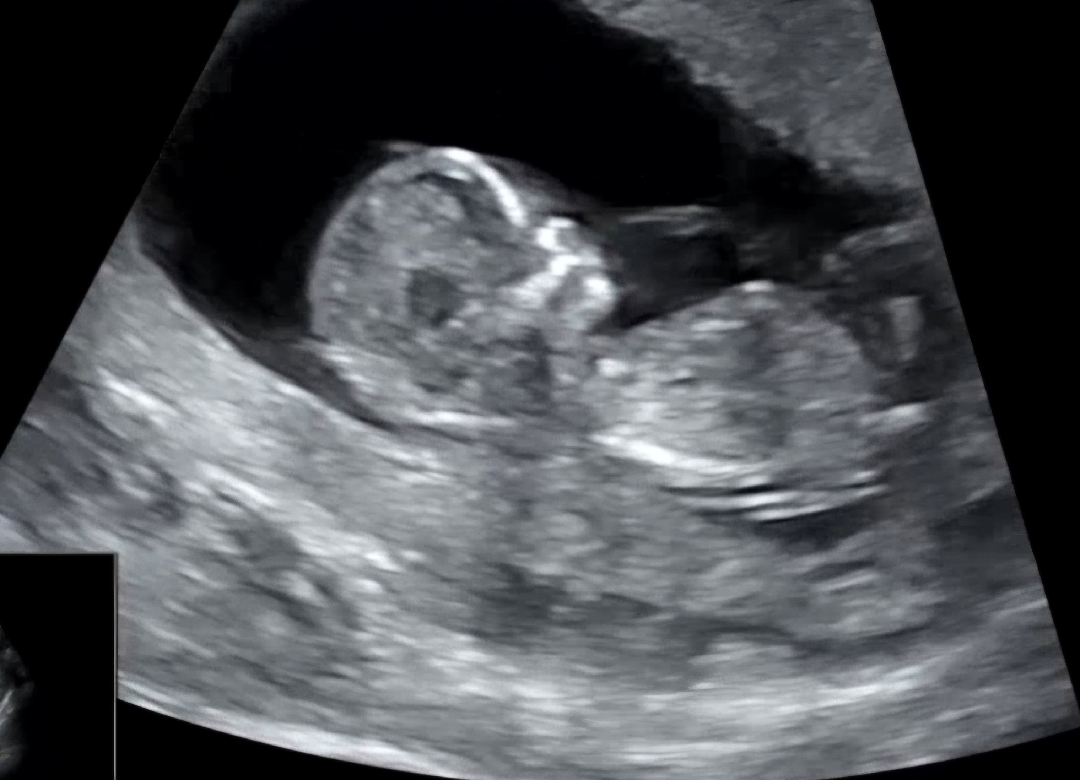

각도법 한번 봐주실래요~? 12주차 3일

안녕하세요~ 각도법 한번 봐주세요 저는 봐도 전혀 모르겠어요 ~ 12주차 3일 입니다 ~

딸이용 ㅎㅎ

딸같아요 ~~